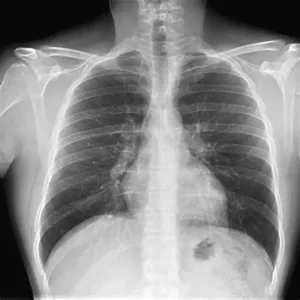

Realização e Interpretação de RX de Torax

1. Realização do Exame Objetivo:Avaliar os pulmões, coração, vasos sanguíneos, ossos torácicos e diafragma. Técnica mais comum: Projeção PA (posteroanterior): paciente de frente para o aparelho, com escápulas afastadas. Projeção lateral: complemento da PA, para avaliação mais detalhada. Preparo: Remover objetos metálicos do tórax e pescoço Em geral,